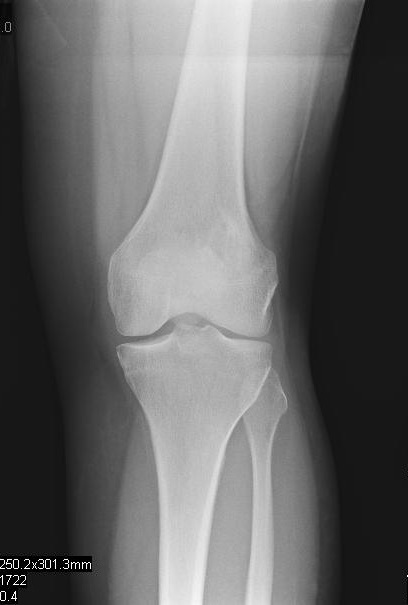

Plain x-ray

• Radiographs of low grade intraosseous osteosarcoma may demonstrate a benign appearance (Fig. 1 & 2).

• However, most lesions show intramedullary extension, cortical violation, and soft tissue involvement.

• The majority arise centrally in the bone, from the medullary cavity and more frequently are methaphyseal.

Fig. 1

Fig. 1 & 2: Plain X Ray of Low Grade Intraosseous Osteosarcoma. AP (Fig. 1) and Lateral (Fig. 2) view of the left knee, shows a mixed sclerotic-lytic lesion in the supracondylar area of the femur. There is no periosteal reaction, cortical destruction, or extraosseous soft tissue mass. The lesion is fairly well circumscribed with a sclerotic margin. The lesion deceptively looks benign